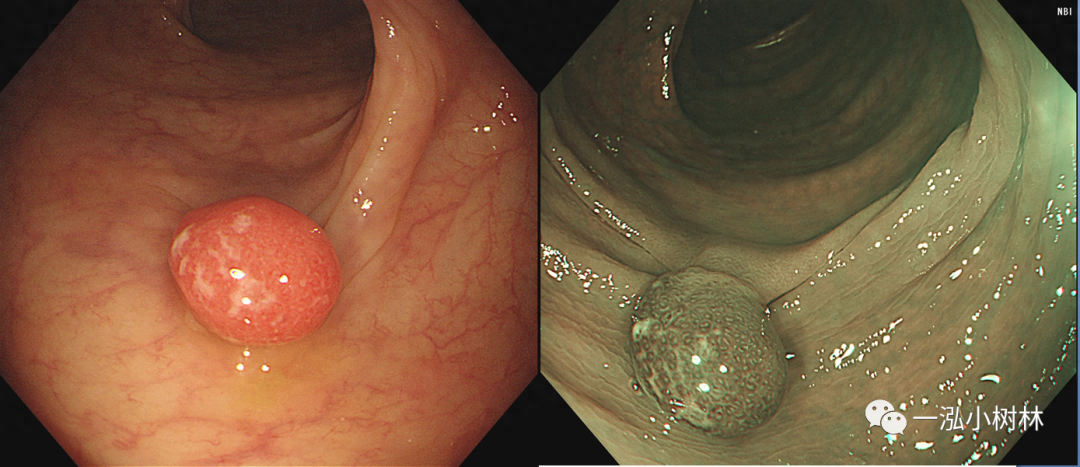

图2 结肠管状腺瘤(Pit Pattern IIIL型)